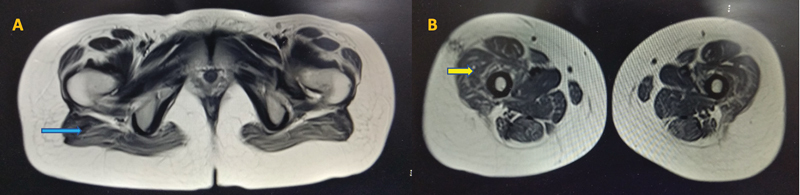

Introduction  ORAI-1 is a plasma membrane calcium release-activated calcium channel that plays a crucial role in the excitation-contraction of skeletal muscles. Loss-of-function mutations of ORAI-1 cause severe combined immunodeficiency, nonprogressive muscle hypotonia, and anhidrotic ectodermal dysplasia. Autosomal dominant gain-of-function mutation causes Stormorken's syndrome, which includes tubular aggregate myopathy along with bleeding diathesis. Methods  This is a description of a genetically confirmed case of ORAI-1-associated myopathy with clinical, histopathological, and imaging characteristics and a detailed literature review. Results  We report an 18-year-old woman who presented with 2-and-a-half year history of slowly progressive proximal lower limb weakness and ophthalmoparesis. Her serum creatine kinase levels were normal. Magnetic resonance imaging of the muscle showed predominant fatty infiltration of the glutei and quadriceps femoris. Histopathological analysis of muscle biopsy was suggestive of congenital fiber-type disproportion (CFTD). Clinical exome sequencing showed novel homozygous nonsense pathogenic variant NC_000012.12 (NM_032790.3): c.205G > T (p.Glu69Ter) in ORAI-1 gene. Conclusion  This report expands the phenotypic spectrum of ORAI-1-related myopathy to include congenital myopathy-CFTD with ophthalmoparesis, a novel manifestation.